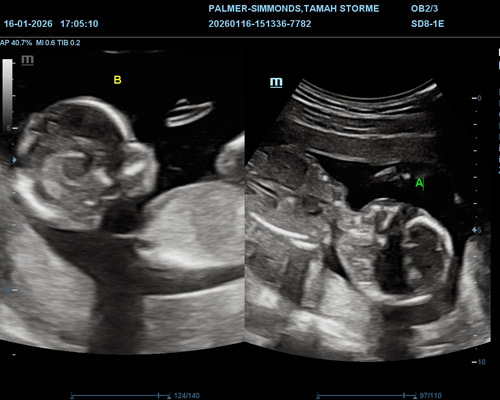

A twin gender scan is a detailed ultrasound designed to identify the gender of both babies as accurately as possible.

Because twins can move frequently and change position, extra care is taken during the scan to ensure each baby is clearly assessed. The sonographer will carefully observe both babies individually and explain what is visible throughout the appointment.

Our Scans